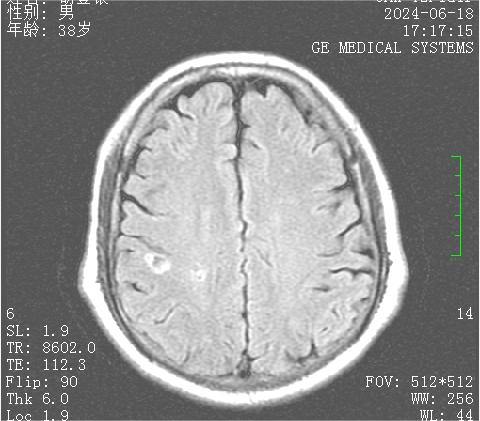

入院查头颅MR提示无新发脑梗死,无明显责任病灶

近日,毕节市中医医院脑病科收治了一名特殊的患者,38岁的胡先生,反复出现左侧肢体无力,就诊于多家医院后被诊断为脑梗死,经药物治疗后仍反复出现一过性左侧肢体无力,遂到我院就诊,入院时左侧肢体不灵活,头晕,眼花,活动时明显,左侧面部麻木,自觉指端冰凉。